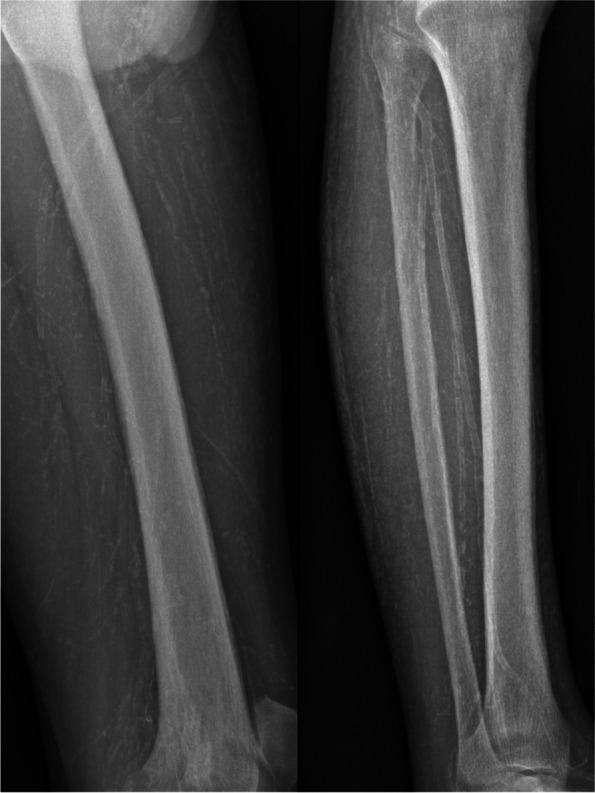

We present a case of a 40-year-old Chinese male patient with ESRD on peritoneal dialysis who developed calciphylaxis with severe painful cutaneous ulcers on the fingers and toes that were managed successfully for 6 months with comprehensive treatment composed mainly of small-dose fractionated sodium thiosulfate.

我们报告了一例 40 岁的中国男性 ESRD 腹膜透析患者,他出现钙化防御,手指和脚趾有严重疼痛性皮肤溃疡,经过 6 个月的综合治疗,主要采用小剂量分段硫代硫酸钠治疗,取得了成功。